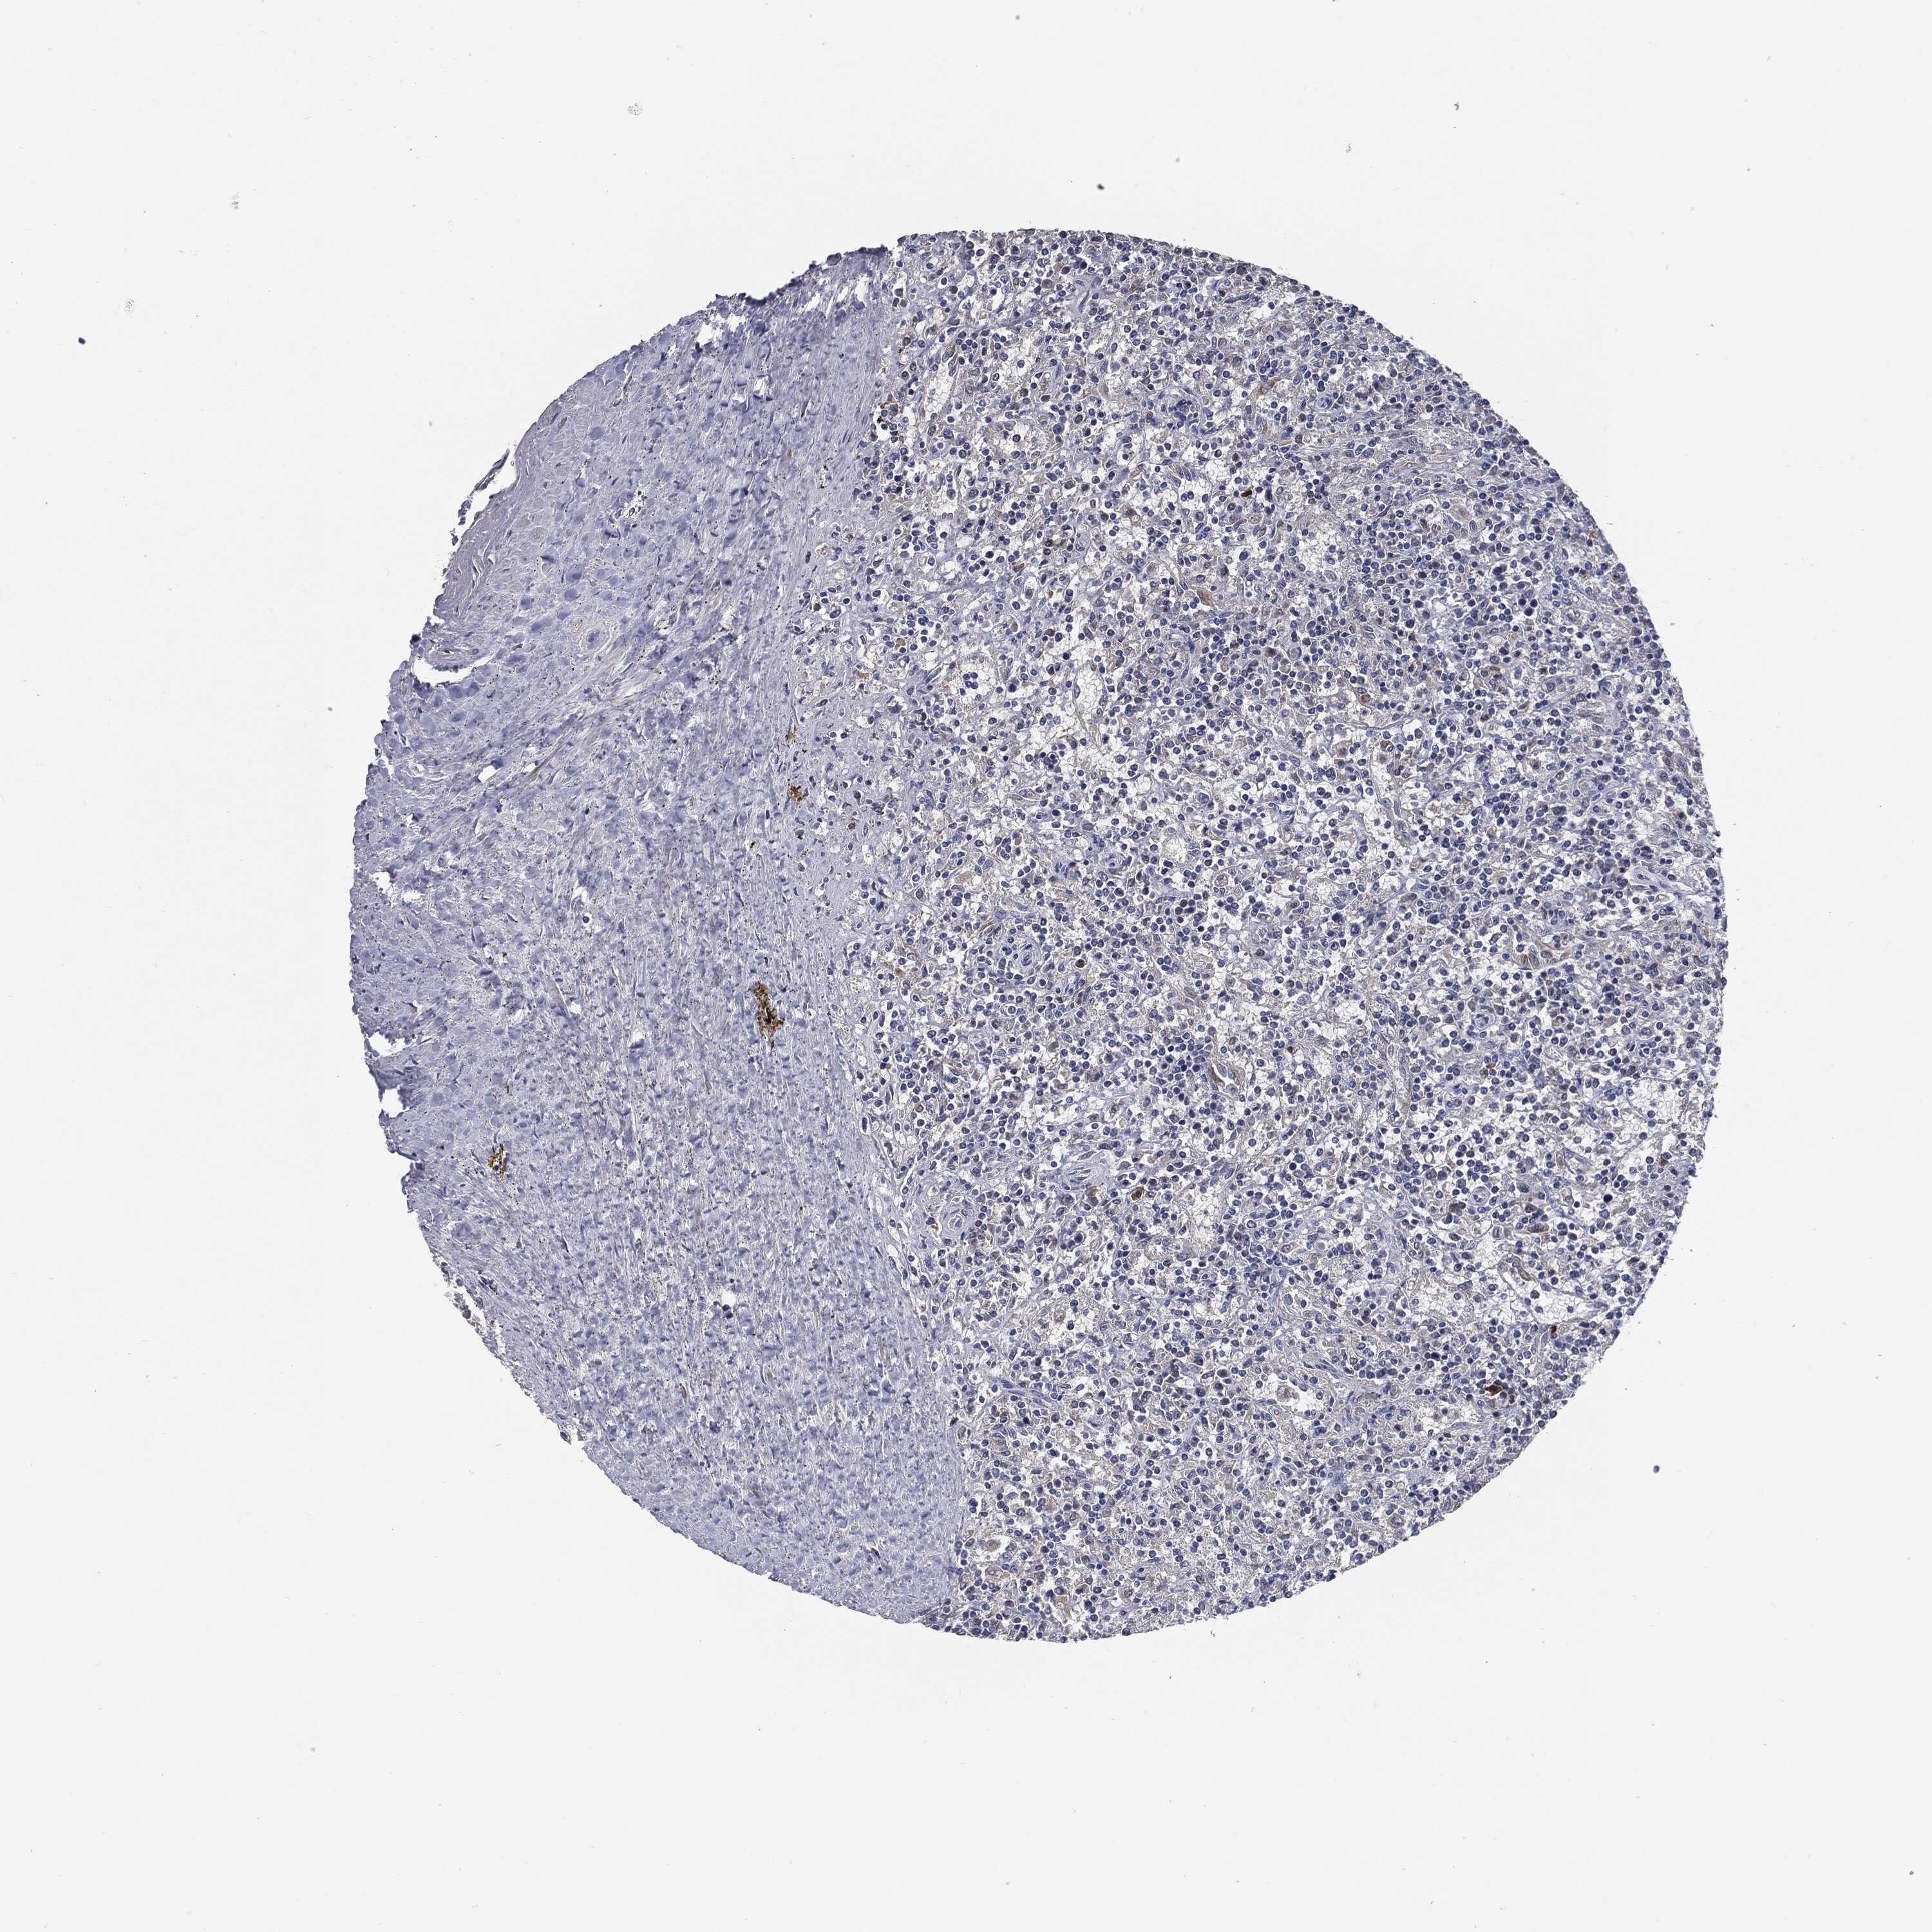

CANCER LYMPHOMA Show tissue menu

LYMPHOMA - Protein expressioni

A mouse-over function shows sample information and annotation data. Click on an image to view it in a full screen mode. Samples can be filtered based on level of antibody staining by selecting one or several of the following categories: high, medium, low and not detected. The assay and annotation is described here.

Each image is clickable and will lead to virtual microscopy that enables deeper exploration of all samples and also displays staining intensity scores, fraction scores and subcellular localization as well as patient and tissue information for each sample.

Antibody HPA020095

Antibody HPA020138

Antibody CAB010878

Antibody CAB080402

Staining

High

Medium

Low

Not detected

Intensity

Strong

Moderate

Weak

Negative

Quantity

>75%

75%-25%

<25%

None

Location

Nuclear

Cytoplasmic/membranous

Cytoplasmic/membranous,nuclear

Hodgkin's disease, NOS

Malignant lymphoma, non-Hodgkin's type, High grade

Malignant lymphoma, non-Hodgkin's type, Low grade